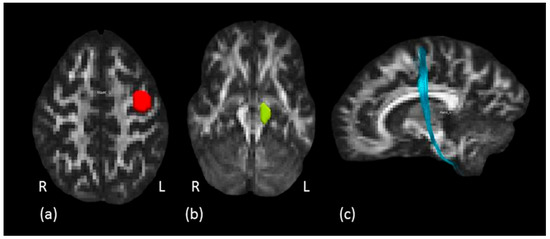

2.3.4. Tractography Dissections of the Internal Capsule, Corticospinal Tract and Hand Motor Tract